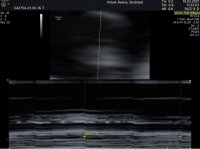

Ble satt tilbake én uke fra 7+1 til 6+1. Hjerteslagene var ikke så raske og noe ujevn så han antok det ikke var lenge siden det begynte å slå. Legger ved mine bilder her så kan de som vil se på de og evt sammenligne med tidligere tul på samme tid. Kanskje det er til hjelp for noen.

Edit: nederste bilde er fra når han målte hjertefrekvens. Prøvde også å laste opp video av hjerteslagene, men fikk feilmelding.

Ble satt tilbake én uke fra 7+1 til 6+1. Hjerteslagene var ikke så raske og noe ujevn så han antok det ikke var lenge siden det begynte å slå. Legger ved mine bilder her så kan de som vil se på de og evt sammenligne med tidligere tul på samme tid. Kanskje det er til hjelp for noen.

Edit: nederste bilde er fra når han målte hjertefrekvens. Prøvde også å laste opp video av hjerteslagene, men fikk feilmelding.